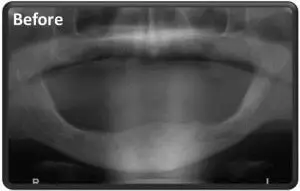

Критическое состояние отсутствия зубов и недостаток челюстной кости в нижней челюсти.